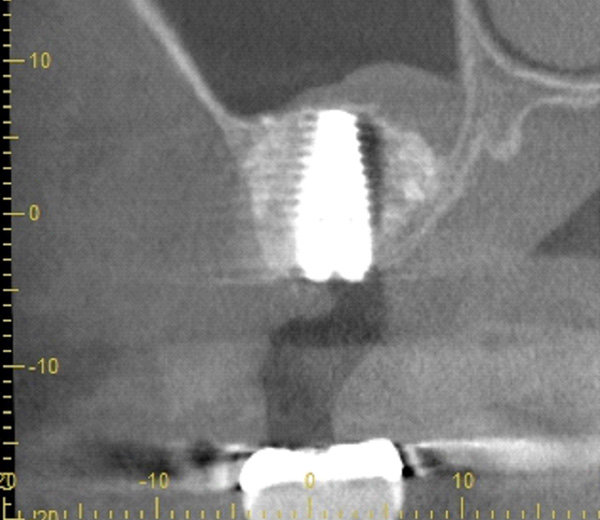

| 主訴 | 右下の歯がないのでインプラントをして欲しい |

| 治療期間 | 約6ヶ月 |

| 費用 | 600,000円 |

| 治療内容 | インプラント、骨造成、結合組織移植、セラミック修復 |

| 治療に伴うリスク | インプラント周囲炎 セラミックの破折、脱離 |